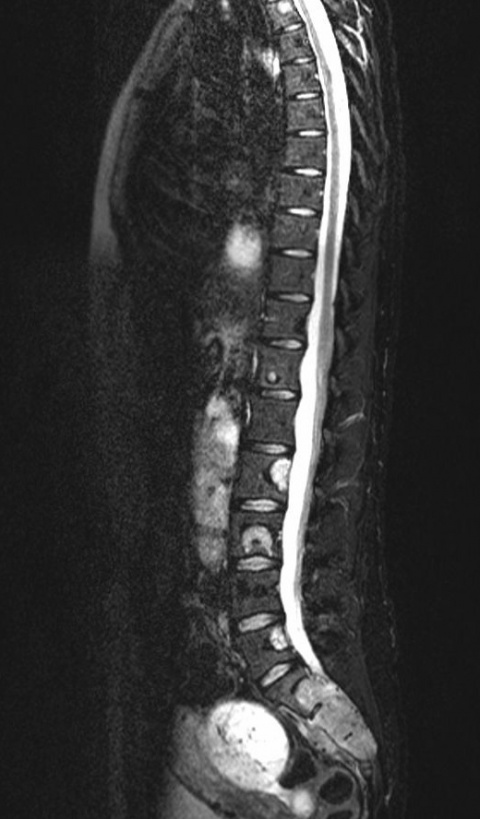

„Knochenmetastasen sind primär Knochenmarkmetastasen, das heißt, sie beginnen im Knochenmark und zerstören erst sekundär den Knochen. Da die MRT die direkte Darstellung des Knochenmarkraums erlaubt, erkennt man mit diesem Verfahren die Metastasen früher als im CT oder beim Röntgen und in der Regel noch bevor es zu einer Destruktion des Knochens gekommen ist“, erklärt Prof. Baur-Melnyk. Daraus ergeben sich große therapeutische Vorteile für den Patienten. Denn je früher die Metastasen entdeckt werden, desto besser können sie auch behandelt werden, zum Beispiel mit Bisphosphonaten, die die Osteoklasten hemmen. Dadurch können die Auflösung und der Abbau von Knochengewebe (Osteolyse) verhindert oder verlangsamt werden und mögliche Komplikationen wie Wirbeleinbrüche oder Querschnittslähmungen bleiben dem Patienten erspart.

Am Universitätsklinikum München erhalten vor allem junge Patienten und solche mit einem unerklärlichen Anstieg der Tumormarker eine Ganzkörper-MRT. „Grundsätzlich ist die MRT das Verfahren der Wahl bei Knochenmetastasen. Wenn ein Patient Wirbelsäulenschmerzen hat und die Anamnese einen Tumor ergeben hat, beginnt die Diagnostik primär mit dem Röntgen, meistens allerdings ohne Erfolg. Dann wird eine lokale MRT gemacht und wenn sich der Verdacht auf Metastasen bestätigt, schließt sich die Ganzkörperbildgebung für das Staging an. Dazu gehörten auch eine CT des Thorax und des Abdomens, um Herde in Lunge und Leber detektieren zu können“, schildert die Professorin.